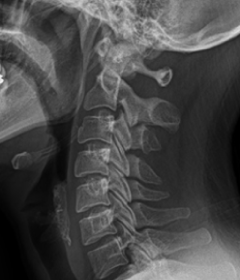

정상적인 목뼈는 C자 형태의 굴곡을 지니고 있습니다. 이를 "전만"이라고 합니다.

그러나 잘못된 자세나 생활습관으로 인해 목뼈의 모양이 일자로 곧게 뻗은 경우는 '일자목 증후군'이라고 하며, 더 심한 경우는 반대 C자 형태 즉, 역 C자 형태의 목을 '거북목 증후군' 또는 '자라목 증후군'이라고 합니다. 이는 의학적으로 경추 후만증으로 일컫습니다.

정상목

거북목